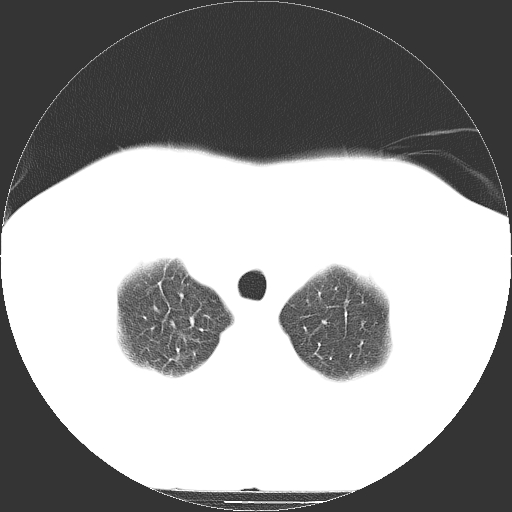

男,65岁,咳嗽、咳痰、发热5天。

慢支 肺间质纤维化合并感染!

支气管扩张合并感染,胸膜肥厚

考虑慢支并感染,肺间质纤维化。

两肺间质性炎症并感染

慢支,肺心病

支持慢性支气管炎伴感染,双侧少量胸腔积液.

两肺间质纤维化,支扩合并感染,双侧胸腔积液

感染,肺间质纤维化。

慢支 肺间质纤维化合并感染

支持慢性支气管、肺间质纤维化合并感染。

慢性支气管炎并感染,支扩,双侧少量胸腔积液.